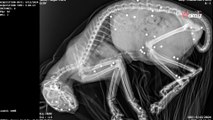

Ils trouvent un chaton avec 35 balles de plomb dans le corps : la communauté se mobilise pour lui rendre justice

Wamiz

il y a 2 ans